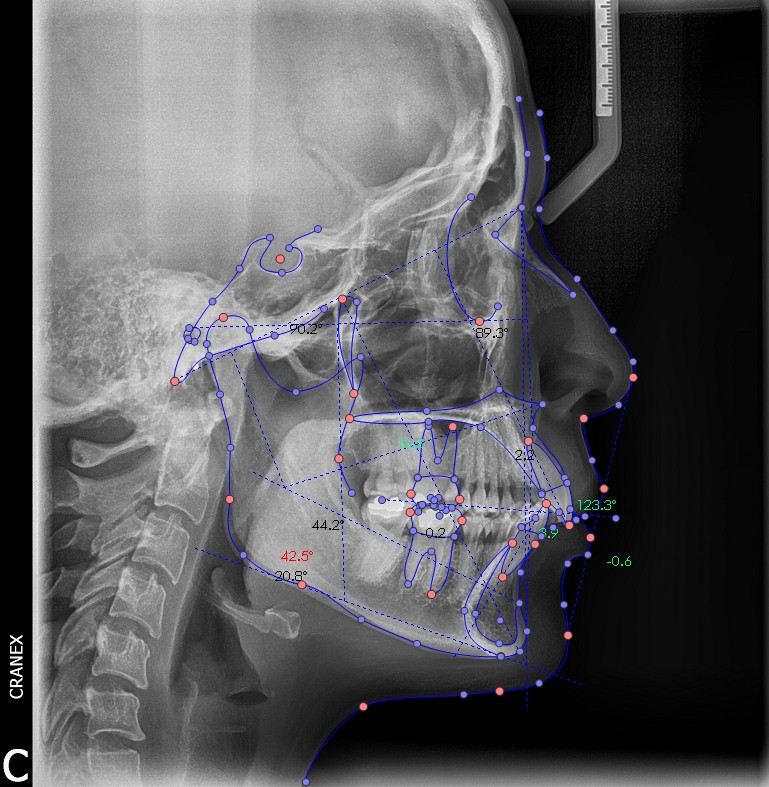

Inicio / Servicios / Análisis radiológico computarizado